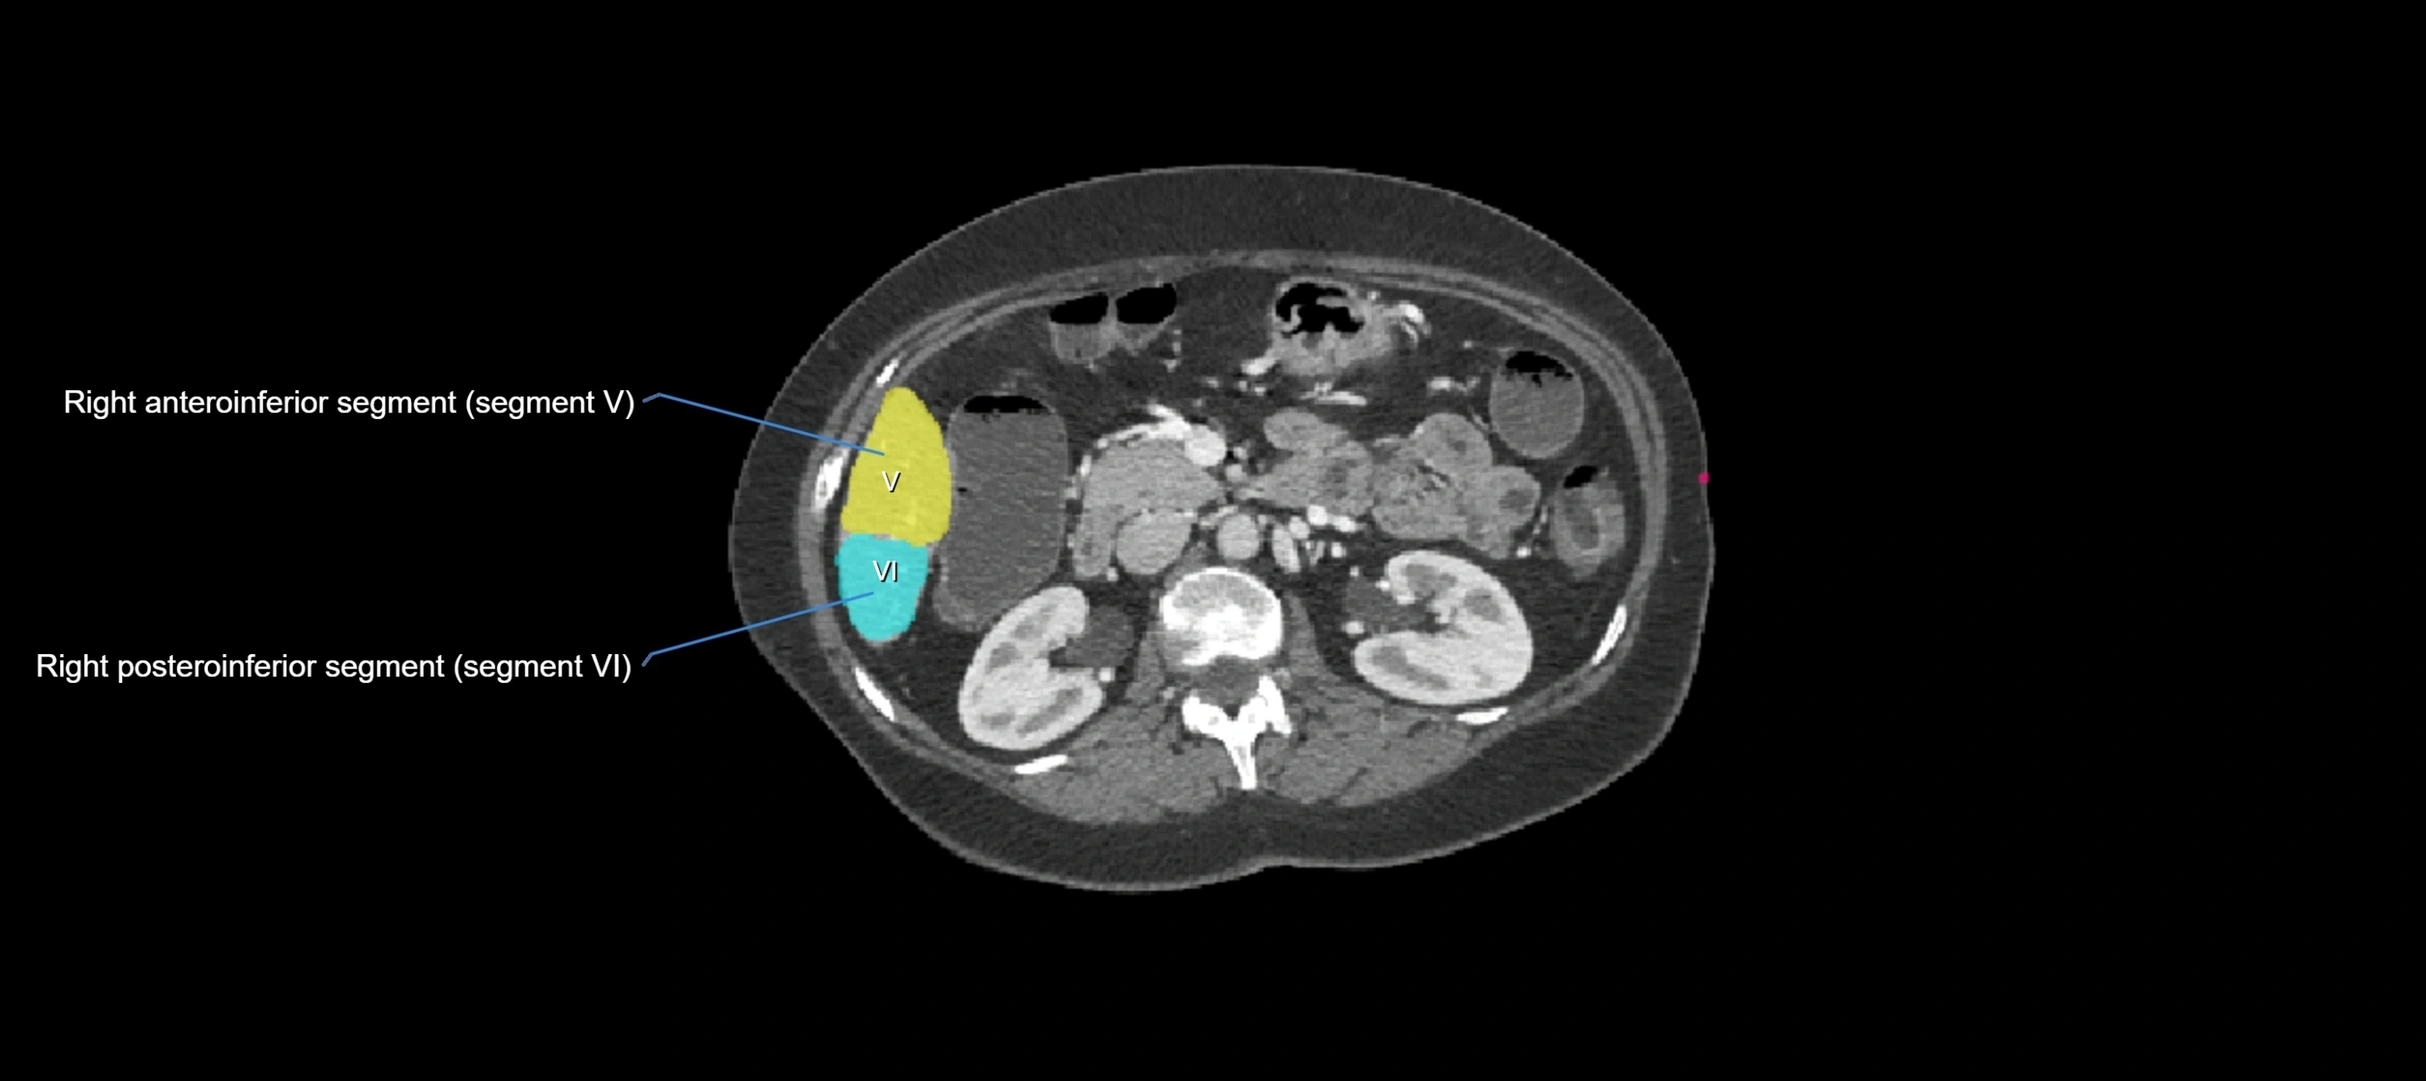

CT Image

image